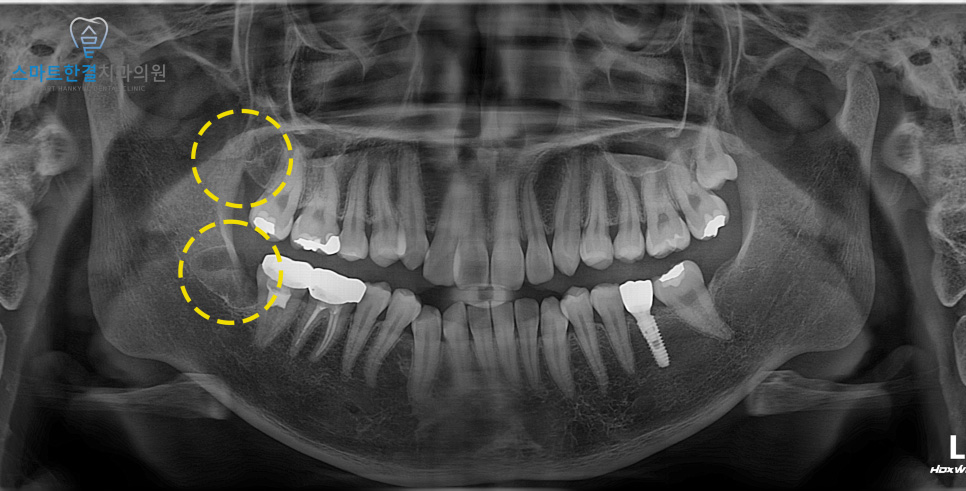

주변 치아 및 조직에 손상 없이

깨끗하게 발치를 한 모습이에요.

아래쪽 사랑니는 누운 상태로 매복되어 있어

잇몸을 절개한 후 치아를 분할하여

발치하는 방식으로 진행하며

위쪽도 같이 진행하였는데요.

이러한 경우, 발치 과정에서

크라운 탈락이나 손상이 발생할 수 있기 때문에

인접 치아에 물리적 압력이 전달되지 않도록

세심한 술식과 충분한 시야 확보를 통해

주의 깊게 발치를 진행하였답니다.